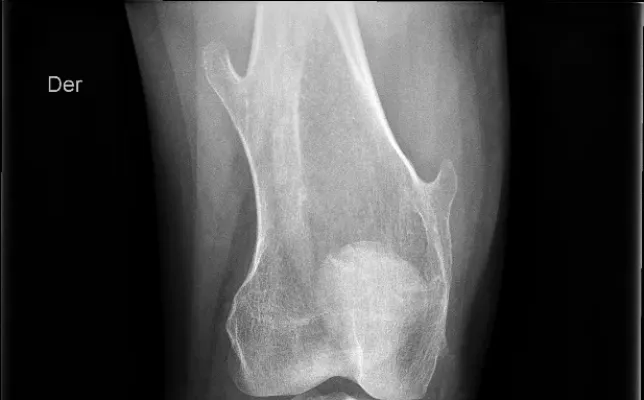

Los casos clínicos ilustran los conceptos desarrollados en los artículos a través de ejemplos reales.

Cada caso propone un análisis sistemático de las imágenes, integrando los hallazgos radiológicos con el contexto clínico y el razonamiento diagnóstico.